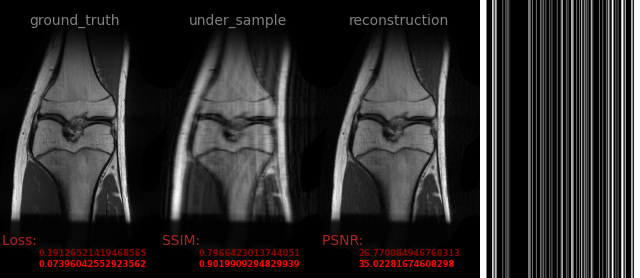

109-b0.png